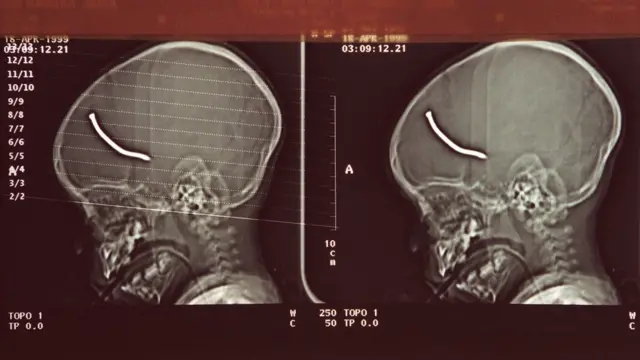

Ранения получили 48 человек. Среди жертв взрыва был годовалый младенец - гвоздь пробил ему череп. Целью нападения было преимущественно чернокожее население Брикстона.